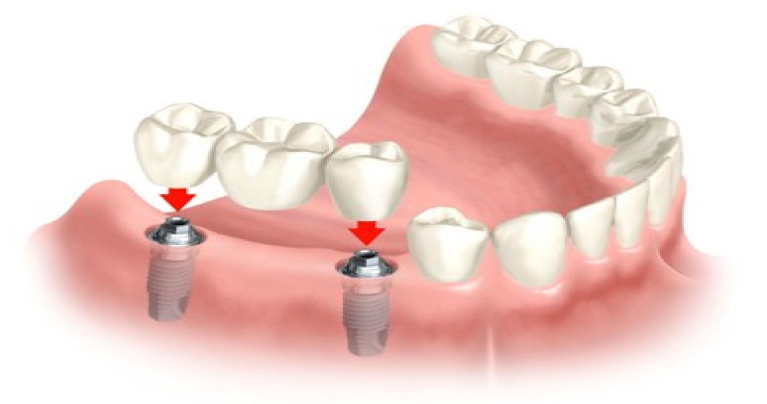

Met meer dan 18 jaar ervaring bieden we een uitgebreid aanbod aan tandheelkundige diensten, waaronder preventieve zorg, algemene tandheelkunde, kroon-en brugwerk en nog veel meer. Onze ultramoderne faciliteit is uitgerust met de nieuwste technologie om ervoor te zorgen dat u de best mogelijke zorg ontvangt.